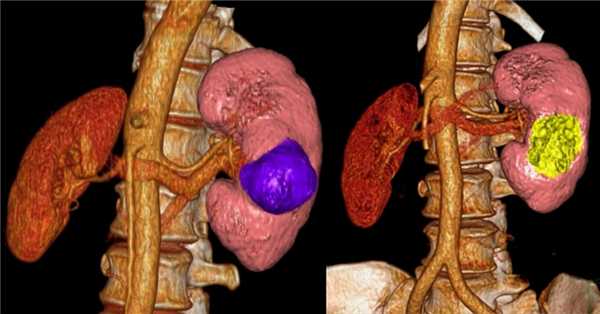

- Томографическое исследование. КТ почки контрастным усилением позволяет обнаружить рак почки любого размера, установить его структуру и локализацию, глубину прорастания паренхимы, инфильтрацию паранефральной клетчатки, опухолевый тромбоз почечной и нижней полой вен. При наличии соответствующих симптомов проводится КТ органов брюшной полости, забрюшинного пространства, костей, легких и головного мозга с целью выявления метастазов.